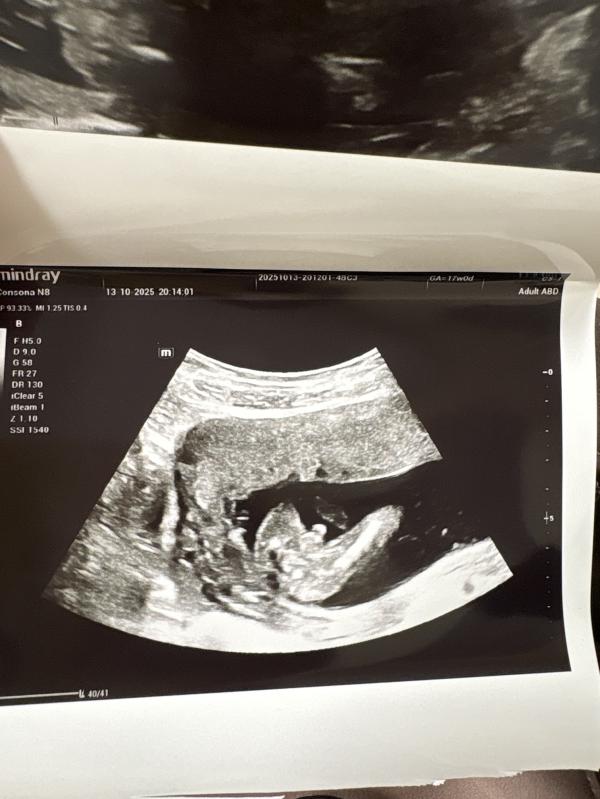

Была на УЗИ, четвертый мальчик! Четвертыыый! 🤣

Я хоть и не узист . Но тут фото супер - сразу видно пацан 👍